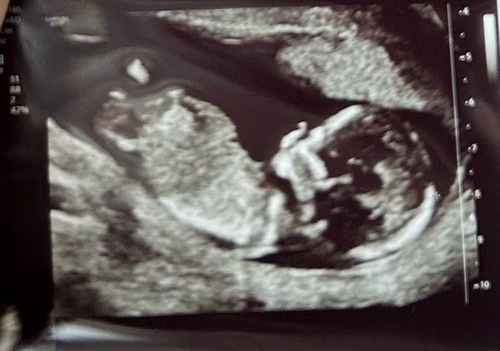

13+5 馃グ wat denken jullie

13 weken en 5 dagen 馃グ Absoluut geen idee of de nub hierop te zien is.. heb ook geen andere foto鈥檚 alleen nog 1 waar alleen het hoofdje op staat.